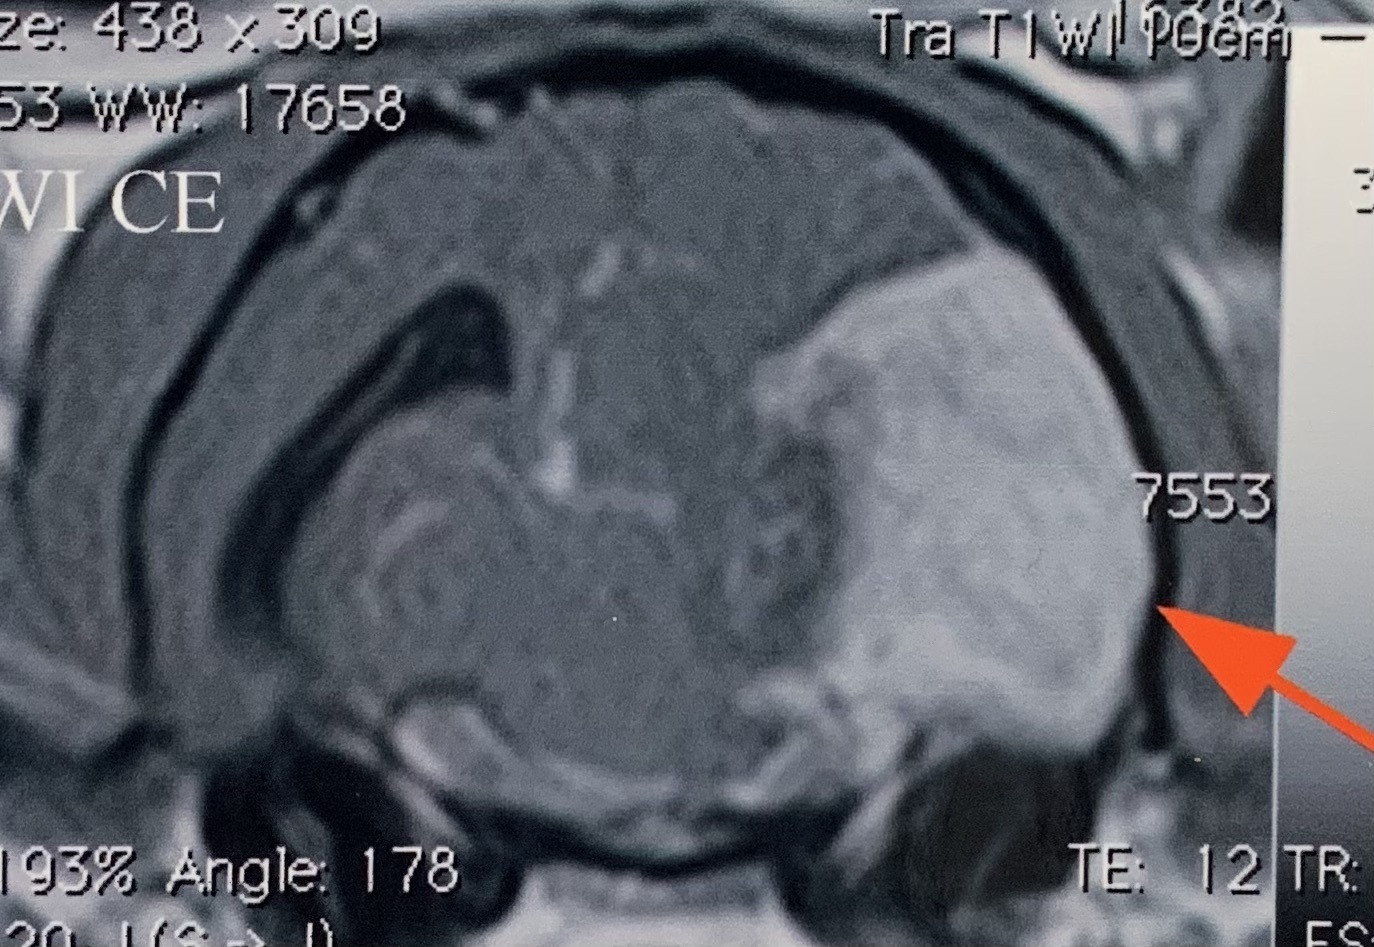

数日前からふらつきとけいれんを主訴に来院された10歳の男の子の猫のMRI画像です。(専門病院へ紹介しMRI検査を依頼しています。)右側頭葉から後頭葉にかけて巨大な脳の腫瘍性病変が発見されました。猫のけいれんの原因としてこのような脳腫瘍が関連することがあります。